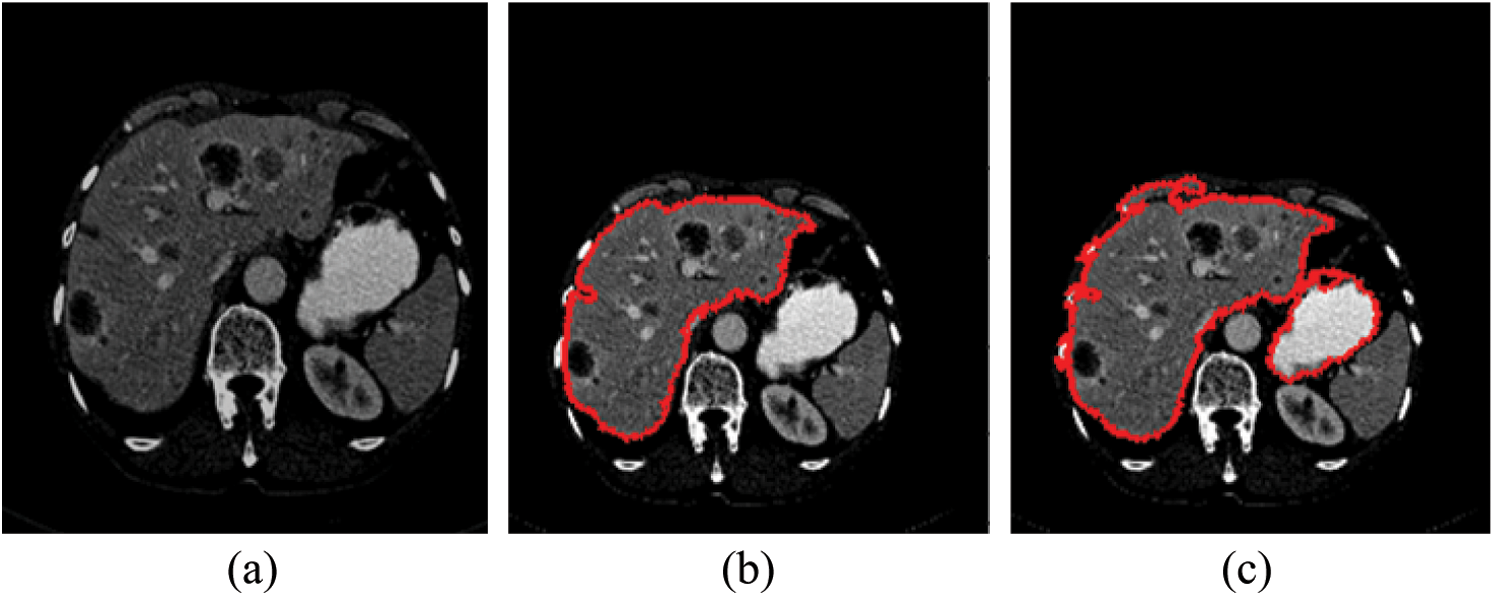

As mentioned in Section 4.1, we implemented our experiment using MICCAI-Sliver07, LiTs17, and 3Dircadb datasets. The MICCAI-Sliver07 dataset has GT for liver segmentation as well as LiTS17 and 3Dircadb datasets. Therefore, we applied FGFCM to segment the liver on all subjects within the used datasets and compared the original FCM. The experimental results of the liver segmntation using FGFCM and FCM are illustrated by Fig. 3 FGFCM achieves higher quality segmentation than FCM. Tab. 1 shows FGFCM based liver segmentation's experimental results, while Tab. 2 shows the segmentation results when original FCM is used.

Figure 3: Liver segmentation (a) Enhanced abdomen image, (b) Liver segmentation using FGFCM, (c) Liver segmentation using FCM

According to Tabs. 1 and 2, FGFCM results in more accurate and reliable segmentation when compared to the original FCM. The mean segmentation accuracy, sensitivity, and specificity were improved by almost 8%, 10%, and 12% respectively when the FGFCM was the segmentation method. This improvement is the consequence of considering pixels’ spatial and grey-level local correlations in the membership function and low noise sensitivity and detail preserving abilities. To reduce the segmentation time, FGFCM reduces the complexity of the segmentation process. This can be achieved by considering the total number of grey levels on the CT scan rather than the size of the scan. The proposed CAD system doesn't require user interaction to identify the trade-off between efficiency and noise suppression. This proves the reliability and automation of the proposed method.

Tumor segmentation experiment was implanted 3Dircadb and LiTS17 datasets only. This because MICCAI-Sliver07 dataset is mainly concerned with the liver segmentation and doesn't include tumors nor their GT. The experimental results for tumor segmentation are demonstrated by Tab. 3. The results in Tab. 3 show that the proposed CAD system achieved high segmentation accuracy for tumor segmentation from CT scans. Fig. 4 illustrates the tumors segmentation from the segmented liver.

Figure 4: The experimental results of the segmntation processes (a) Outlined liver, (b) Segmented liver using FGFCM, (c) Outlined tumors and (d) Segmented tumors binary masks